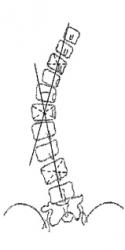

Метод Фергюссона (Fergusson) для определения угла сколиотической деформации во фронтальной плоскости.

Угол сколиоза образован пересечением линий, соединяющих геометрические центры нейтральных позвонков с геометрическим центром позвонка, расположенного на высоте сколиотической дуги.